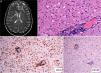

Se trata de una mujer de 47 años con lesiones eritematodescamativas de 6 años de evolución, que tras 4 biopsias no concluyentes fue diagnosticada de MF estadio ib. Durante 4 años de seguimiento recibió tratamiento con corticoides tópicos potentes, PUVA, interferón y bexaroteno oral. En el último año desarrolló lesiones tumorales (fig. 1A), con presencia en sangre periférica de un 14% de células de Sézary (<1.000/μL) y TAC toracoabdominopélvica sin hallazgos relevantes (estadio iib). Se decidió aumentar la dosis de bexaroteno oral y realizar radioterapia local, con respuesta parcial. Una biopsia cutánea de una lesión tumoral de rápido crecimiento mostró transformación de célula grande (TCG) con positividad acusada para CD30 (fig. 1B-D), no presente en las biopsias previas. Escasos meses después la paciente refirió alteración de la memoria reciente, así como ánimo depresivo. En la exploración física se apreció nistagmo y dismetría, por lo que se realizó TAC cerebral urgente que descartó enfermedad aguda, y nueva TAC toracoabdominopélvica en la que tampoco se hallaron alteraciones significativas, pese a lo cual, se decidió ingreso hospitalario. En la RMN cerebral se apreció alteración difusa de la señal de la sustancia blanca, especialmente a nivel frontal (fig. 2A), compatible inicialmente con encefalitis infecciosa. El estudio del líquido cefalorraquídeo mostró pleocitosis linfocitaria T sin atipia, con cultivos negativos. Finalmente se realizó biopsia cerebral, que mostró una infiltración por linfoma T CD4+ CD8− (fig. 2 B y C) sin TCG y presencia de células CD30+ aisladas (fig. 2D). Inició tratamiento quimioterápico según protocolo BAM (carmustina, metotrexato y citarabina). Sin embargo, se produjo una progresión de la enfermedad, con aparición de lesiones metastásicas renales confirmadas mediante biopsia y múltiples nódulos pulmonares indicativos de metástasis. No se apreció TCG ni en tejido cerebral ni renal, por lo que en este caso en concreto se trató de un fenómeno localizado a nivel cutáneo. Desgraciadamente, la paciente falleció debido a una insuficiencia respiratoria aguda, 3 meses después de iniciarse la clínica neurológica.

A: Micosis fungoide en fase tumoral. B: Detalle de la biopsia de una lesión tumoral en la que se aprecia un infiltrado linfoide difuso de célula grande en dermis (HE, ×400). C: Tinción inmunohistoquímica que demuestra predominio de linfocitos T CD4+ (CD4, ×400). D: Expresión del antígeno CD30 en las células del infiltrado linfoide (CD30, ×400).